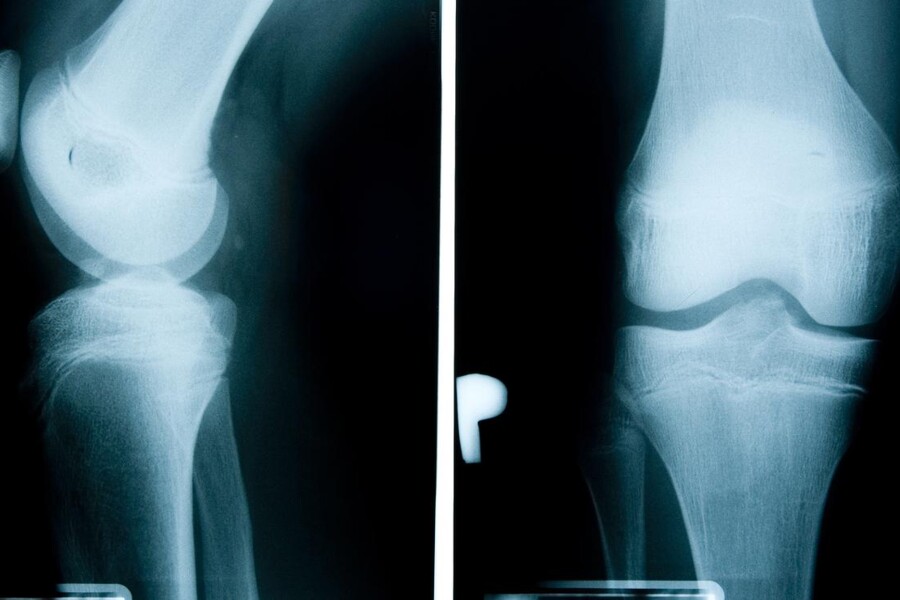

Lékař diagnostikuje nemoc na základě popisu příznaků a vyšetření dítěte. Obvykle nechá provést dítěti rentgenové vyšetření, aby vyloučil jiné možné příčiny příznaků. Bolest, otok a zvýšená citlivost obvykle ustoupí, jestliže je dítě v klidu a omezí fyzickou aktivitu. Lékař zpravidla předepíše léky proti bolesti, které zároveň potlačují zánět - např. ibuprofen. Vhodná je také dočasná ortéza, která znehybní postižené koleno, a posilování svalů v blízkosti kolena speciálními cviky. V období dospívání potíže většinou ustanou.